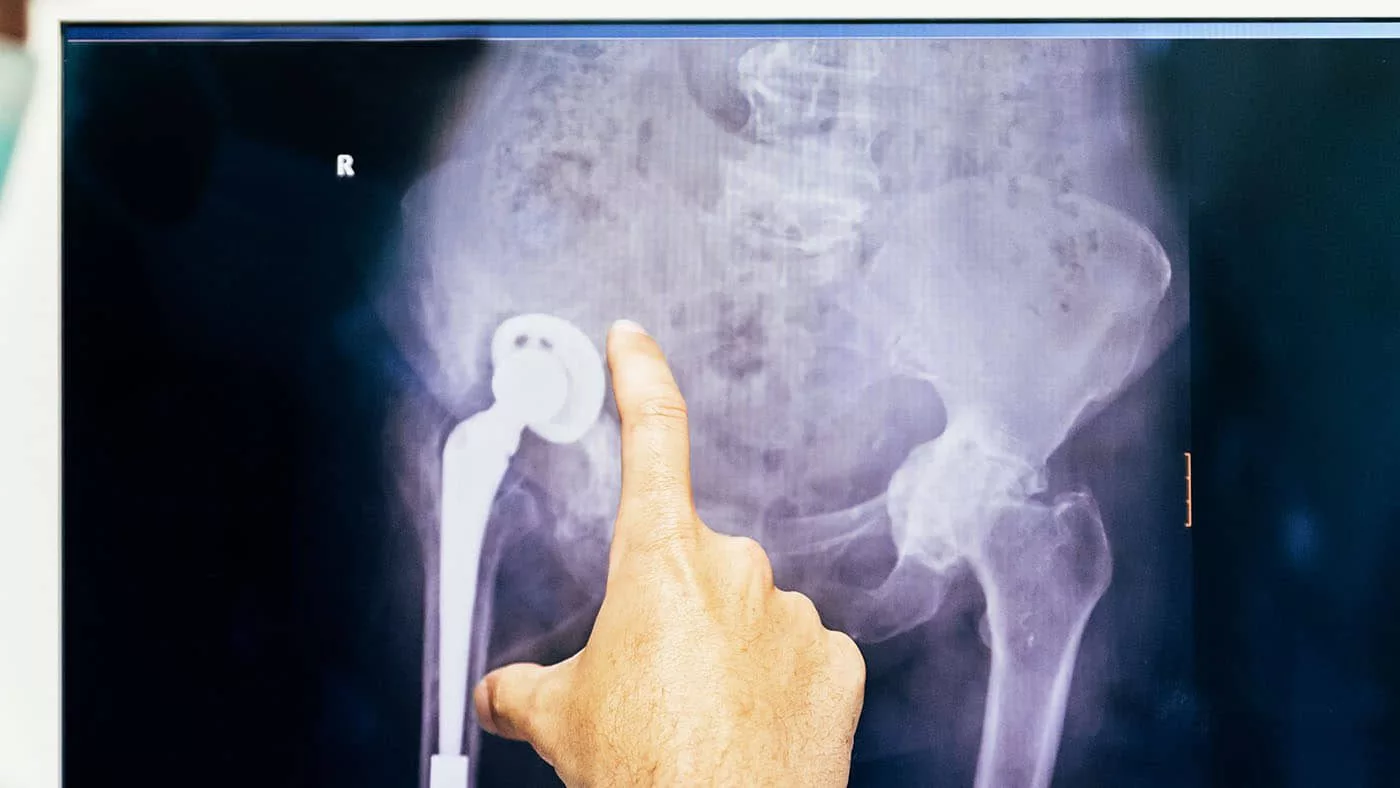

Бедренный компонент под названием «ножка Вагнера» впервые использовали при операции по эндопротезированию хирурги ВКО. Как рассказали в Управлении здравоохранения области, процедура осложнялась наличием пластины на бедренной кости пациентки.

— Операция осложнялась тем, что сначала нужно было убрать с бедренной кости пластину. Это было сложно сделать без повреждения кости, но мы сделали. Для замены расшатанного бедренного компонента мы решили использовать «ножку Вагнера». Это бедренный компонент эндопротеза, специально разработанный для деформированных бедренных костей, — объяснил заведующий отделением ортопедии ВК областной больницы Думан Бакербеков.

— «Ножку Вагнера» мы использовали впервые в регионе. Эти дорогие высокотехнологичные комплектующие раньше поставляли только в клиники Алматы и Астаны. В этом году мы смогли их приобрести для проведения ревизионного протезирования, чтобы наши пациенты могли получать необходимую помощь, не выезжая за пределы ВКО, — добавил Думан Бакербеков.